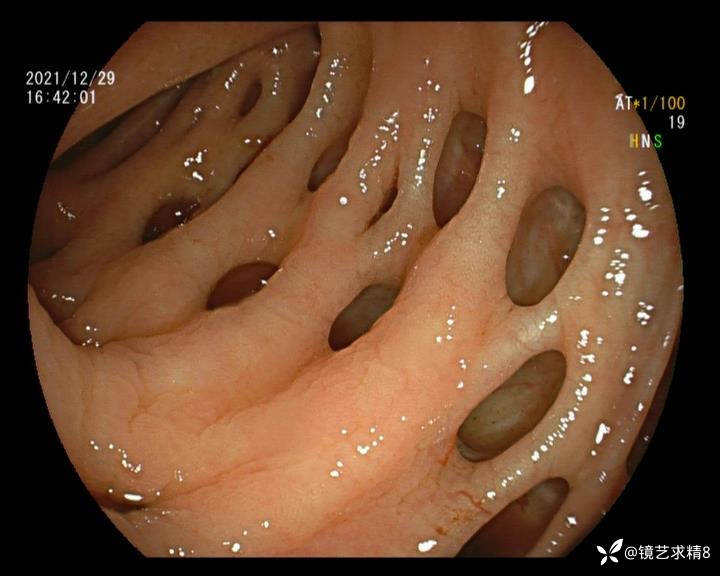

结肠内违建⥤结肠多发憩室☞续

小壮兵爱学习等 2人推荐看到手机存有2年前一个病例仅有的3张图片,因为没有更多的图片就只描述了多发憩室这个内容,没想到浏览量很快上万,很多都和我一样第一次见这么多憩室的结肠,就不得不想要把2年前所有的片子拷贝出来分享。该病例憩室合并外源性因素成为憩室出血的原因。后面附有代表性的全结肠图片。

患者以消化道出血入院,胃镜未见异常,肠镜进入乙状结肠就看到很多憩室,同时还看到肠腔用清肠药后移动下来1枚尖锐的枣核,这么多憩室,这个枣核扎入憩室的机会非常大,推测应该是掉入一坑🕳就算出来还会有很多坑🕳🕳🕳等着,掉入憩室内很容易刺破血管,这可能就是消化道出血的原因,继续前进可以看到有一些憩室内翻,还有一些息肉,问题来了,那么多憩室,犯罪分子是抓住了,它在那些憩室内作过案?到达回盲部后挨个冲洗,但憩室大小又不足以把镜头进入憩室内观察,针对有血块的憩室冲洗后可疑出血的以夹子闭合或套扎,取出枣核,如果有锥形透明帽可能钻入憩室精准电凝效果更好,若内镜下操作失败介入治疗成功率更高,经内镜下治疗后观察未再出血出院。